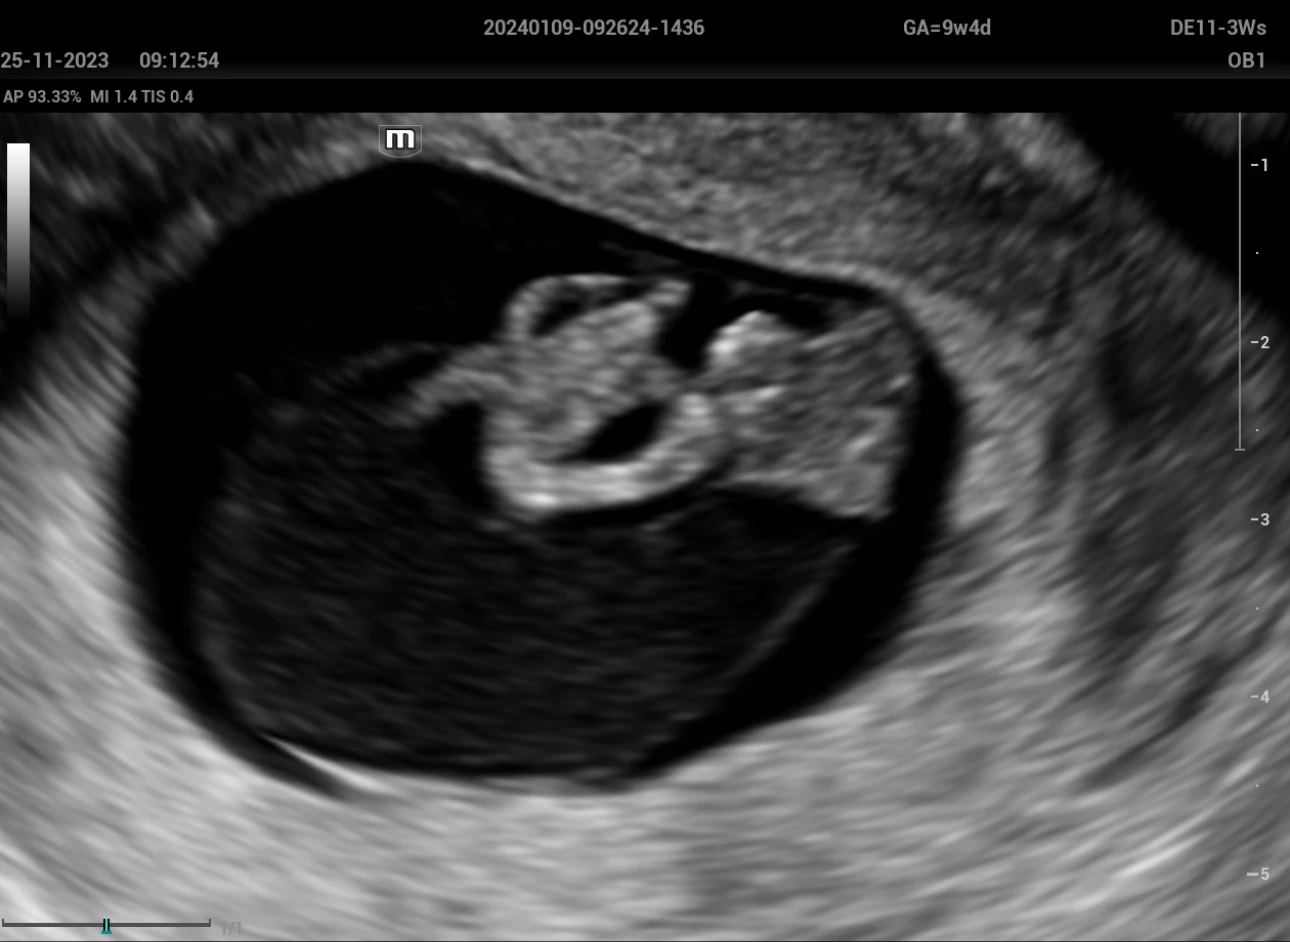

A woman of 22 years old, first pregnancy, marital status domestic partner, level education secondary schooling. The medical history includes a laparoscopic cholecystectomy 3 years ago and the first sexual relationship at the age of 15. The patient went to the Fetal Medicine Service of the Perinatal Maternal National Institute with a private ultrasound exam in which they consider a 9-week gestation + pleural effusion, so she was scheduled for a transvaginal ultrasound, which was performed with an Ultrasound System, model Nuewa I9 (Mindray) with an endocavitary volume transducer DE11-3Ws, observing a 26 mm CRL embryo, with cardiac activity of 171 B.P.M. who presents anencephaly (Figure 1), omphalocele (Figure 2), ectopia cordis (figure 3), hydrothorax and scoliosis (figure 4); Therefore, Body stalk is diagnosed, suggesting the interruption of the pregnancy as there is no prognosis for extrauterine life.

Anencephaly

Figure 1: Anencephaly